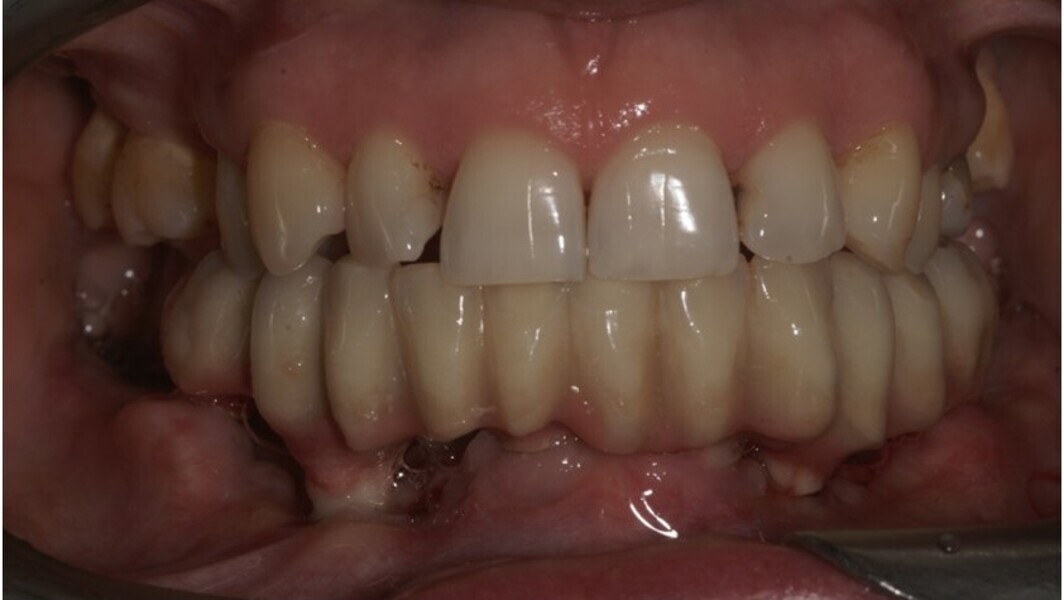

Natychmiastowa implantacja i zaopatrzenie protetyczne pacjentów z zaawansowaną chorobą przyzębia